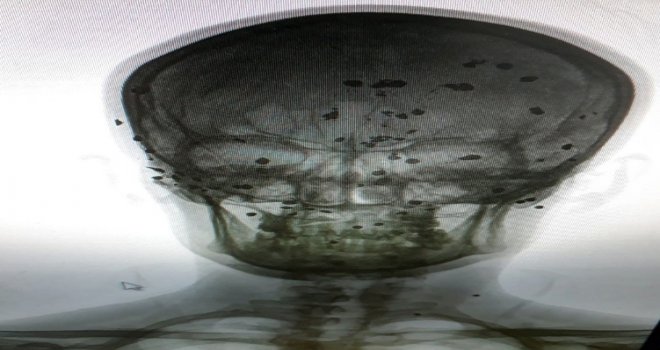

Cuma Araz, çektirdiği röntgen filmlerinde kafatasındaki saçmaların çok net göründüğünü söyledi.